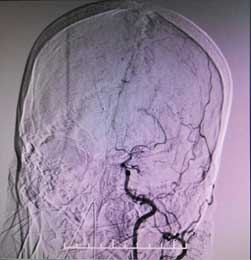

其實,大腦內(nèi)的血管就像樹木的樹杈,主干的血液通過分支達到大腦的各個地方,但煙霧病人的主干是堵塞的。主干堵塞后,長出無數(shù)根毛細血管來替代,從血管造影上來看,如同煙囪里冒出的裊裊炊煙,因此被形象地稱作煙霧病。

顱內(nèi)煙霧狀血管